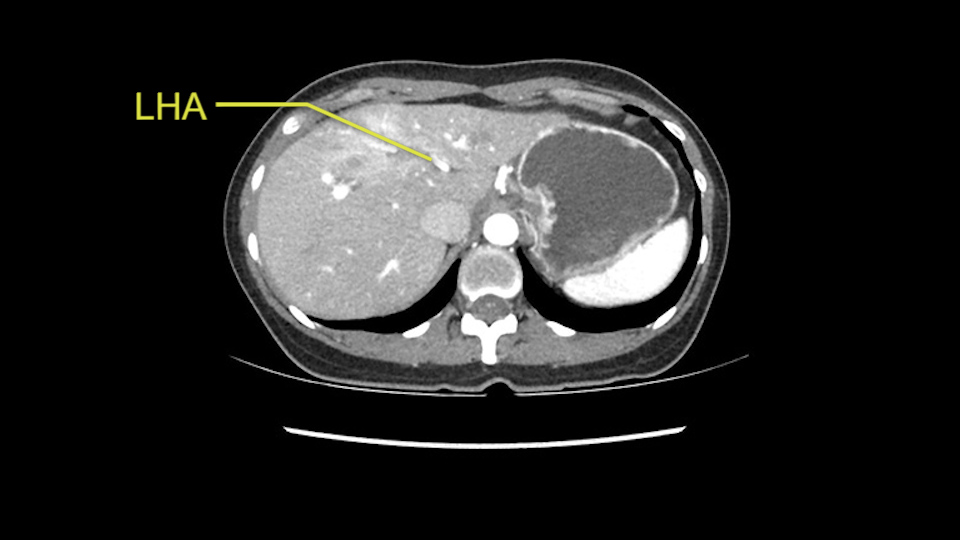

Anatomically, to plan for a left lateral segmentectomy, it’s relatively easy as far as liver surgery goes. I know that I'm going to be looking for the left hepatic vein which will be divided at some point either towards the end at the back near the vena cava or through the middle of the left lateral segment.

Inflow is not usually an issue except if there are as a replaced or aberrant left hepatic artery. In which case you’d be careful when you mobilize the left lateral segment.

So I have to say that I would do this open, not laparoscopically because of the size of the tumor itself. Upper abdominal incision. Almost certainly, we’d be able to flip this very exophytic lesion up. Intraoperative ultrasound will show the relationship of the tumor and the left portal vein but the dissection at the base of the liver, as I look at things here, I can see the left hepatic artery which sneaks up to the left of the portal vein, should be out of harm’s way so I can take the Segment 2-3 left hepatic artery. The left portal vein is somewhat compressed. But by the time you pull the liver up a bit, you’ll be able to pull that left portal vein out to length and get a good margin on it.

The second is the left hepatic artery. The tumor is displacing the arterial system. So one of the important points which we need to see intraoperatively is to identify and preserve the right artery very carefully and identify the left hepatic artery for ligation.